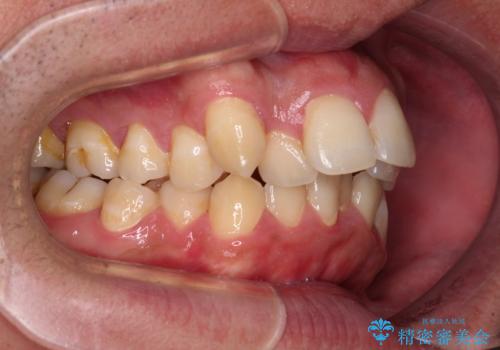

- デコボコと前歯の突出感を気にして来院された患者様です。

舌の突出癖などにより上顎前歯が前方に突出し、さらに歯列幅が狭小になっている状態でした。

また、上顎歯列全体が下顎に対して前方位に位置していました。

上顎歯列幅を側方に拡大するとともに、歯列全体を後方に移動させるためのアンカースクリューと補助装置を使用し、上顎左右第一小臼歯2本、下顎左右第二小臼歯2本、計4本を抜歯し、ワイヤー装置にて矯正治療を行うこととしました。